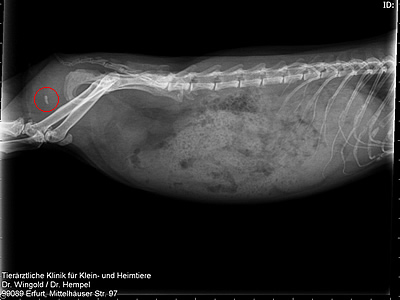

- Auch auf diesem Rötngenbild ist der Blasenstein (roter Kreis) des Meerschweinchens gut zu erkennen.

Vielen Dank an Dr. Wingold http://www.kleintierklinik-erfurt-ilversgehofen.de/,Simone und Rieke für Bereitstellung der Bilder.